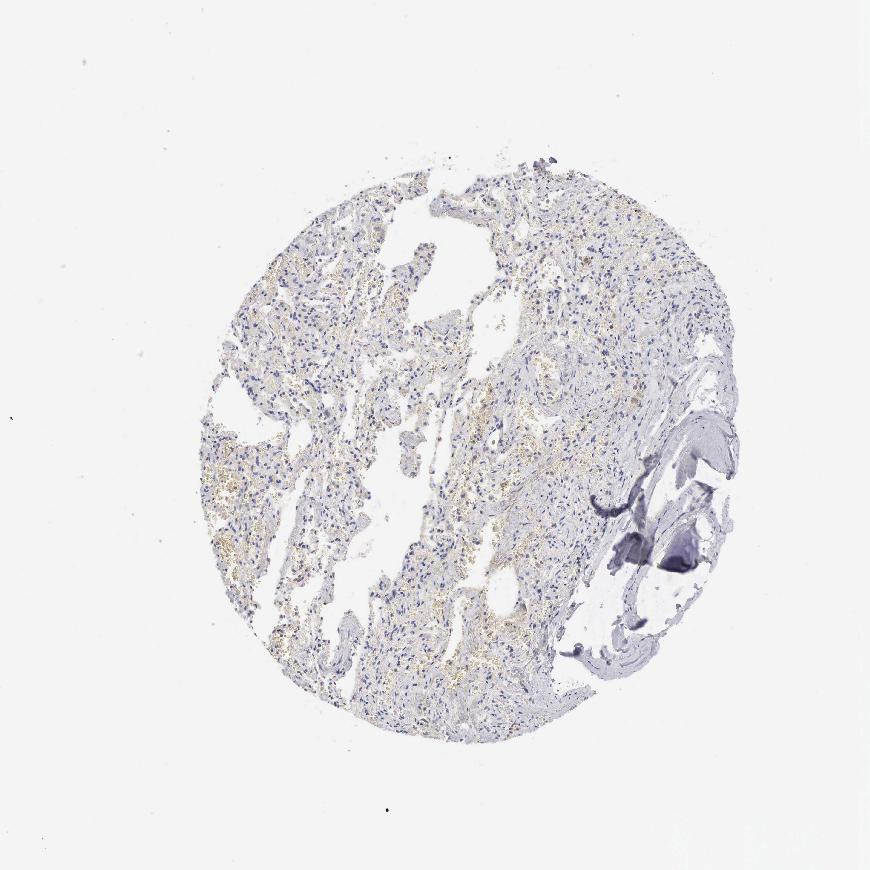

SOFT TISSUE - Expression summary

Protein expression

Soft tissuei

On the top, protein expression in current human tissue, based on all annotated cell types, is reported with the units not detected (n), low (l), medium (m) and high (h). Underneath, protein expression in each annotated cell type are reported using the same units.

Protein expression data is based on knowledge-based annotation. For genes where more than one antibody has been used, a collective score is set.

If knowledge-based annotation could not be performed for a gene, no data is displayed here. View antibody staining data further down this page.